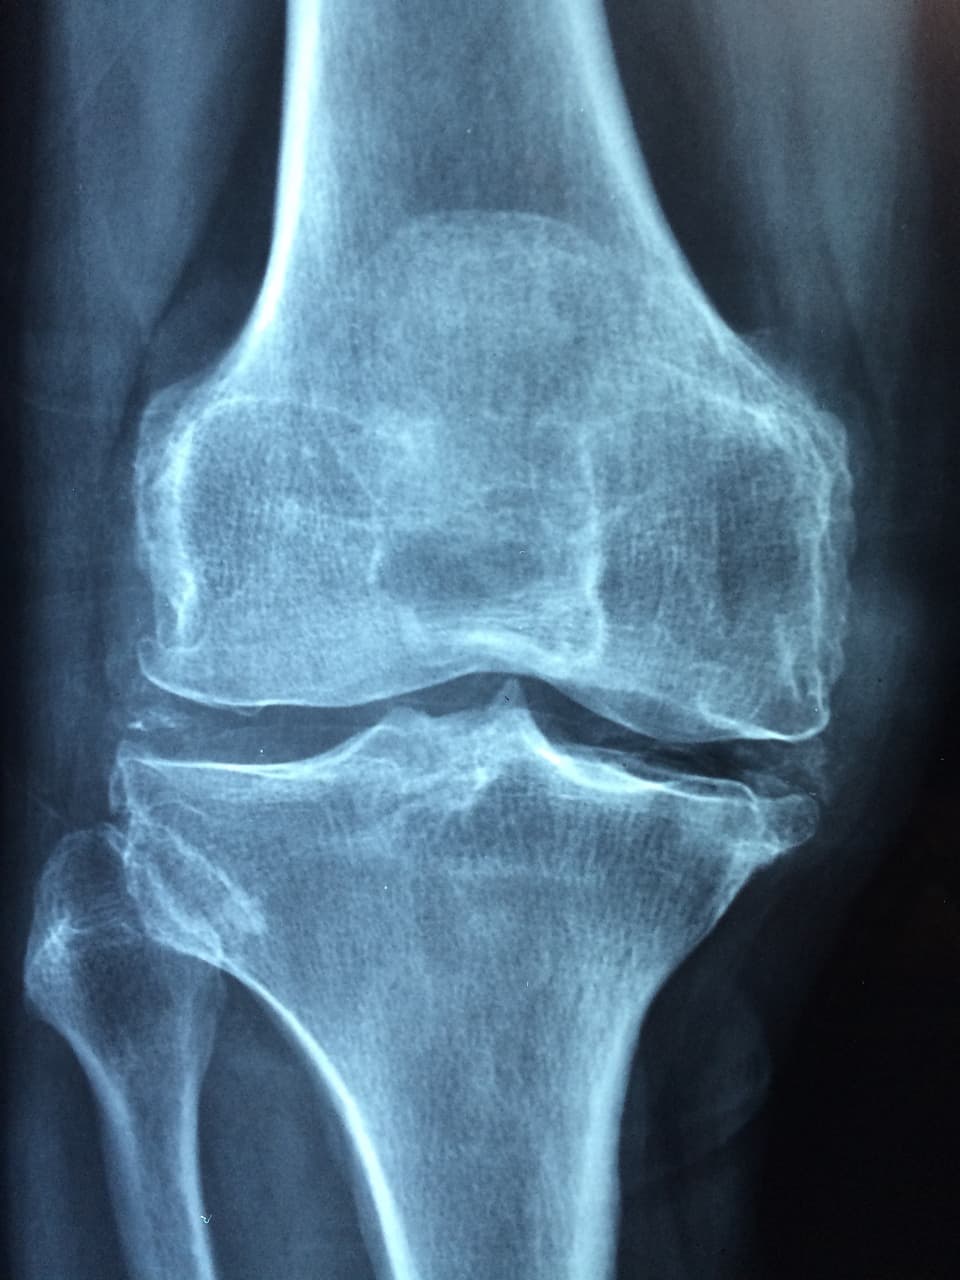

골다공증의 진단

골다공증 진단은 종합적인 임상 평가로 시작됩니다. 의료 기록, 이전 골절 여부, 골다공증 가족력, 생활 방식 및 약물 사용 등을 평가하여 위험 요인을 파악합니다. 또한 의료인이 신체검사를 통해 전반적인 뼈 건강을 평가하고 키의 감소나 척추 곡률과 같은 골다공증의 시각적인 징후를 식별할 수 있습니다.

골다공증 진단의 중추적인 요소인 이중 에너지 X선 흡수측정법 (DEXA) 검사는 뼈 미네랄 밀도를 측정하는 비침습적인 영상 기술입니다. 검사 중에는 낮은 복사량의 X선 스캐너가 특정 부위, 일반적으로 척추, 골반 또는 전완 등을 통과합니다. DEXA 검사는 뼈 밀도를 정밀하게 측정하여 당신의 뼈 밀도를 동일 성별의 건강한 젊은 성인과 비교합니다.

결과는 T점수로 표시되며, 당신의 뼈 밀도가 평균적인 최고 뼈 밀도와 비교됩니다. -2.5 이하의 T점수는 골다공증을 나타내며, -1.0에서 -2.5 사이의 점수는 골다공증의 전단계인 골다공증을 나타냅니다. 특정 경우에는 뼈 건강을 종합적으로 평가하기 위해 추가적인 진단 검사가 필요할 수 있습니다. 이러한 검사에는 발뒤꿈치의 정량적 초음파 검사 (QUS), 손목 및 손가락 뼈의 말단 이중 에너지 X선 흡수측정법 (pDXA) 또는 정밀한 뼈 밀도와 구조 측정을 위한 정량적 컴퓨터 단층 촬영 (QCT) 스캔이 포함될 수 있습니다. 혈액 검사도 칼슘, 비타민 D 및 호르몬 수준을 평가하여 뼈 손실에 기여하는 기본 요인을 평가합니다.